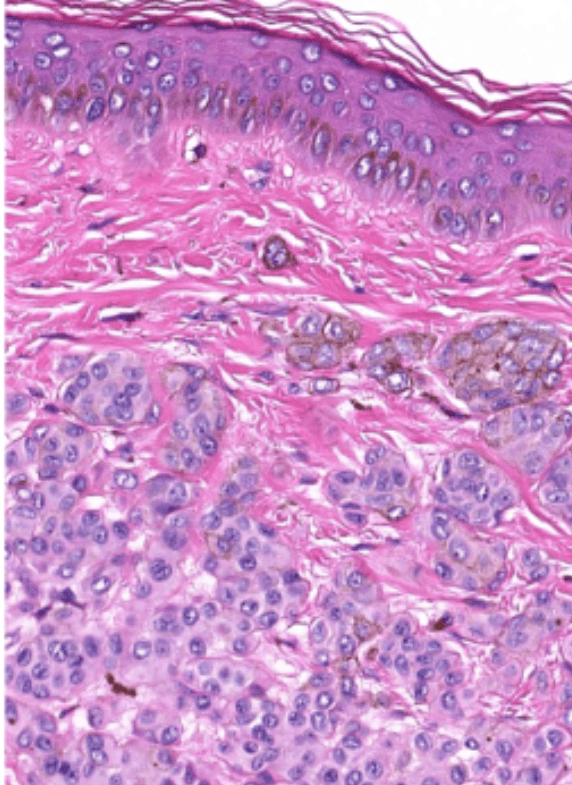

- Organ: Skin

- Diagnosis: Dermatofibroma

- Description

- A poorly circumscribed dermal tumor with peripheral collagen trapping

- Areas of hypercellularity or hypocellularity

- Fascicles or whorls of spincle cells or histiocytic cells

- May have epidermal hyperplasia or basal hyperpigmentation

(melanin pigment)

(circumscribed/infiltrative)

(pagetoid spread)

(hyperchromatic也可)